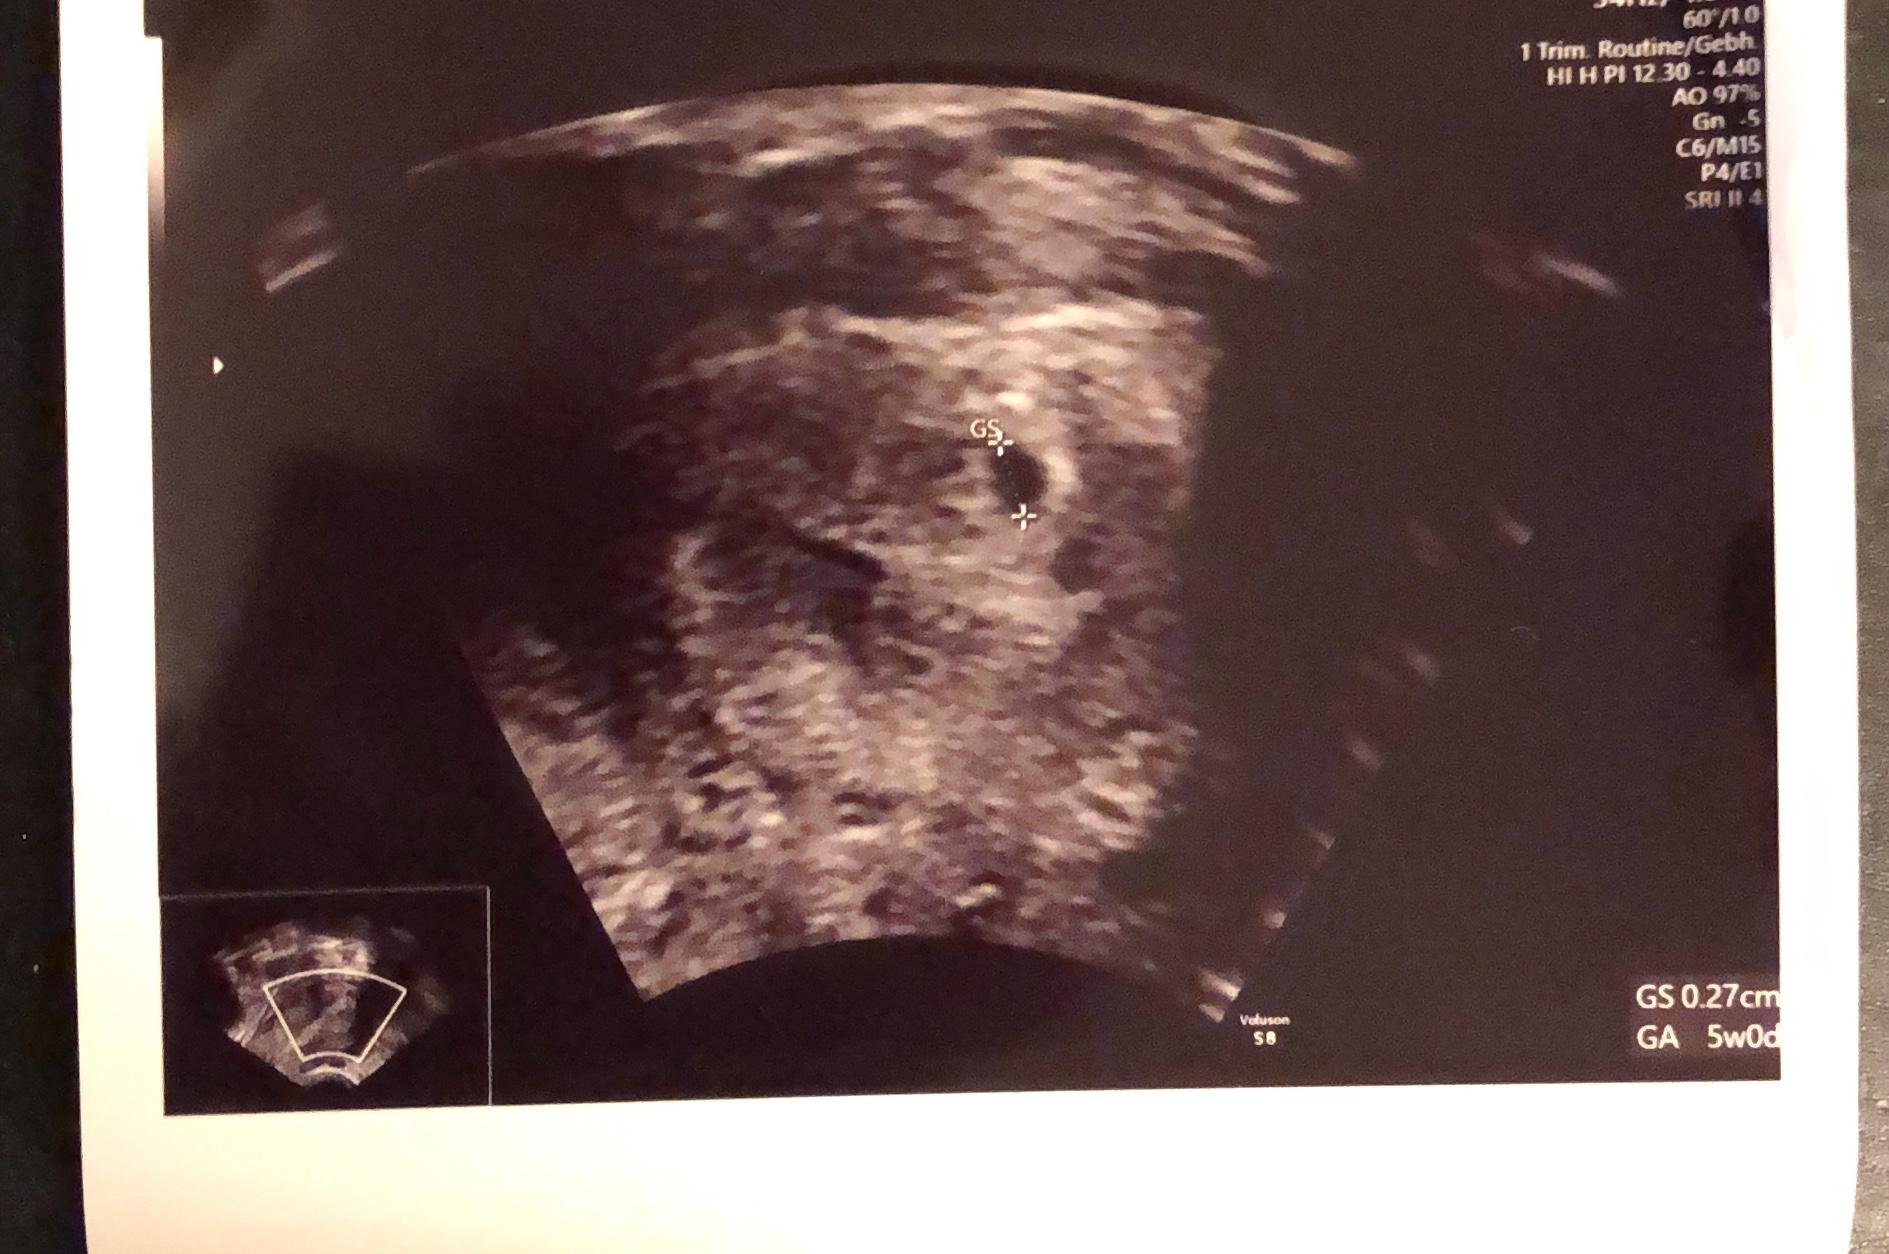

Schwangerschaft 5 Woche 5 Ssw Ultraschallbilder